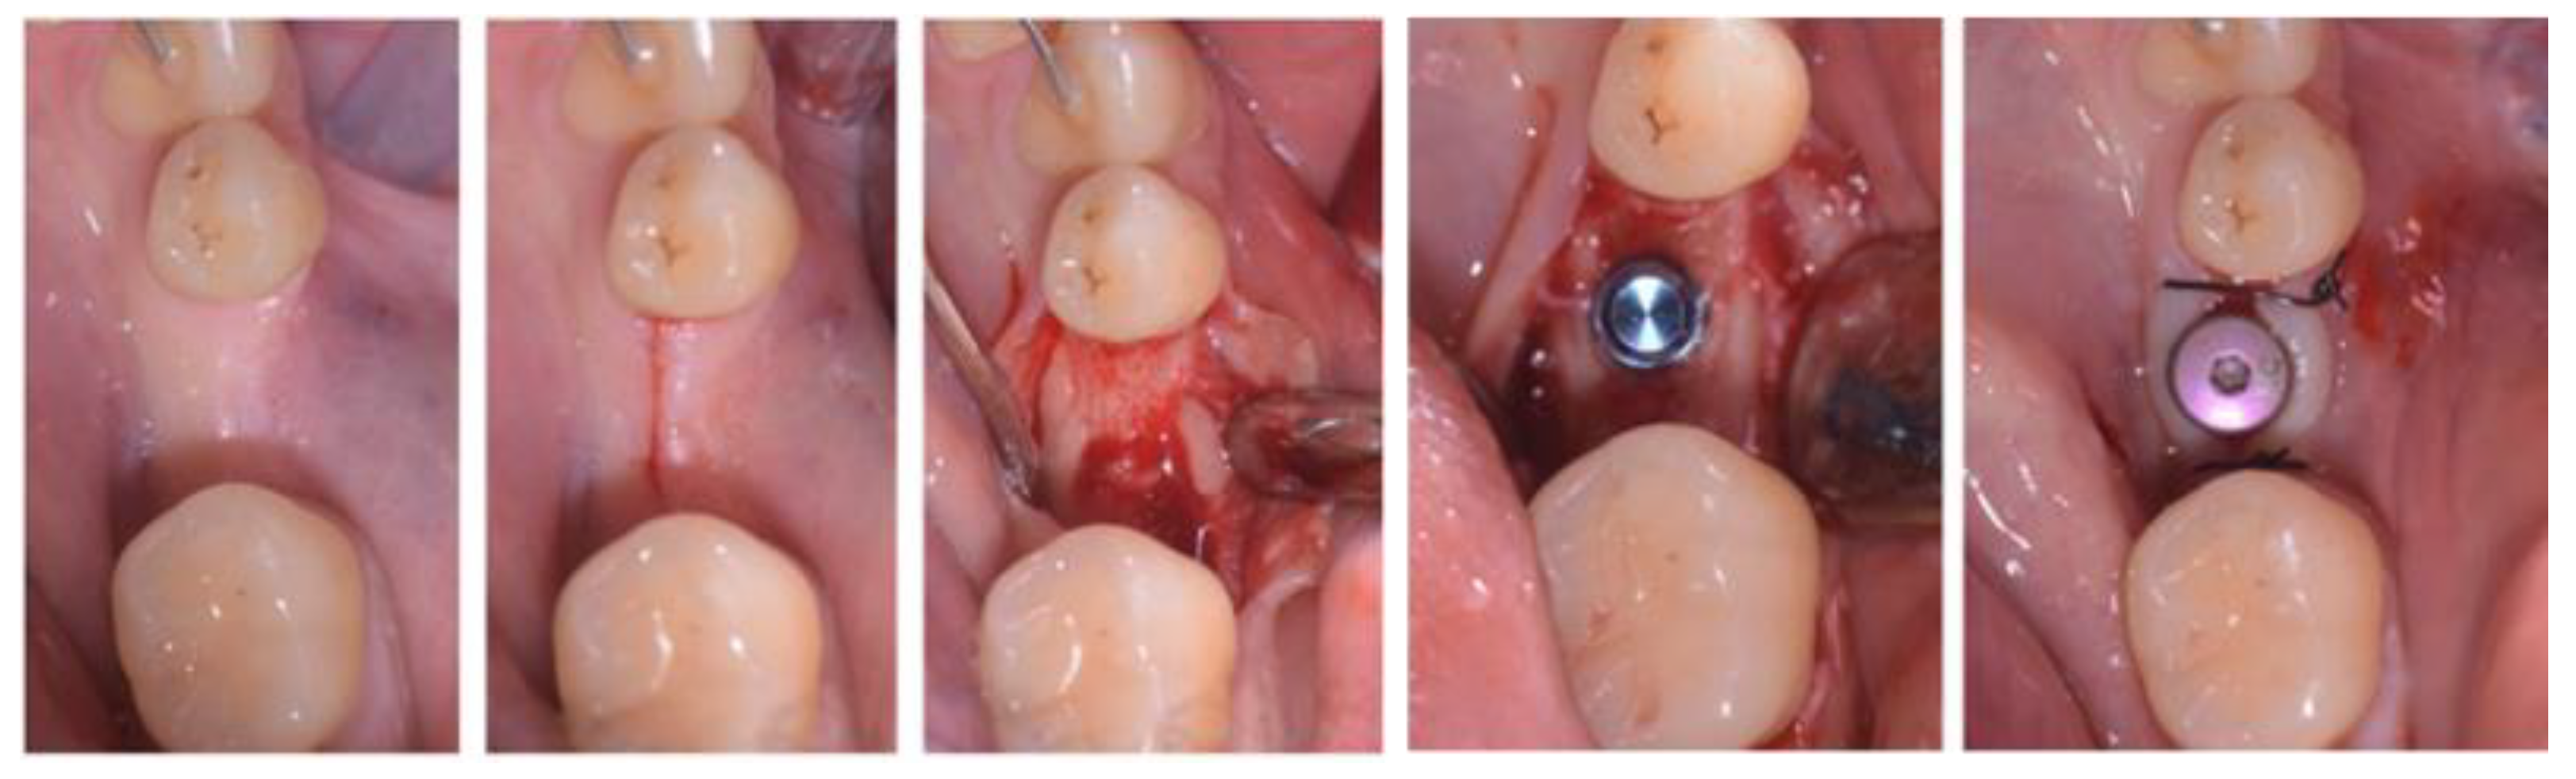

- Case 1:

- Case 5: